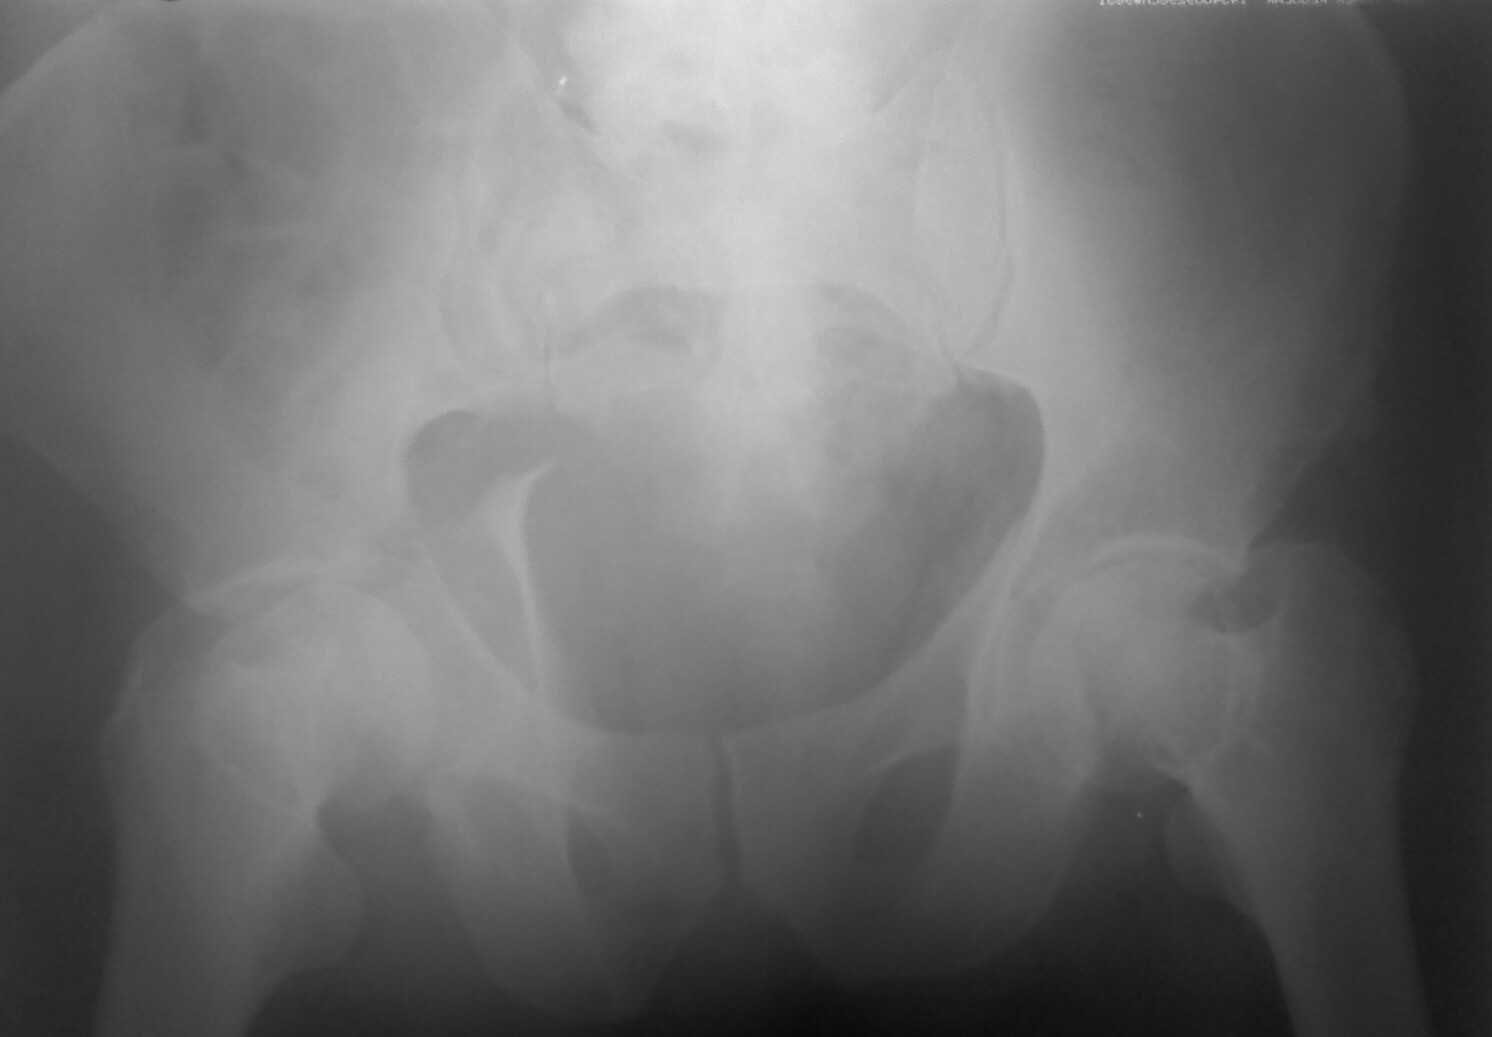

Добрый день ув.коллеги. Теперь подробнее.В нашем отделении находится пациент с тяжелой сочетанной травмой (множественные переломы ребер, тупая травма живота с повреждением печени, селезенки) с нашей стороны тяжелая травма таза.С момента травмы прошло 3 недели.при поступлении в экстренном порядке пациентом занимались хирурги, затем проводилось интенсивное лечение в реанимации. сначала боролись с двухсторонним гемопневмотораксом, потом с пневмонией. В течении всего времени пациент находился в положении по Волковичу, других мер не принималось (почему не знаю). На сегодняшний день состояние больного стабильное, удовлетворительное.пневмония разрешилась, проблем по животу и легким нет, по анализам компенсирован. На представленной R-мме и КТ если я правильно расценил: справа имеется полный внутрисуставной двухколонный перелом, низкий вариант(С2)., слева поперечный перелом вертлужной впадины(В10) без смещения.(извините за качество, снято с телефона)Хотелось бы услышать ваше мнение, предложения по поводу лечения перелома костей таза. Стоит ли оперировать левую вертлугу? Чем предпочтительнее зафиксировать перелом справа? Заранее спасибо. С ув.Андрей.